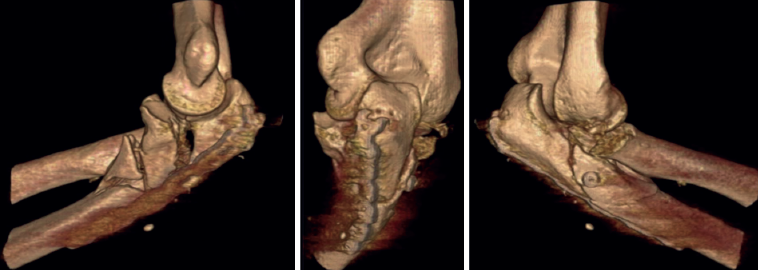

A pesar de que no existe un consenso en relación con la clasificación de las fracturas-luxaciones del codo y ateniéndonos al concepto fractura-luxación transolecraneana, en estas lesiones debe existir una fractura intraarticular del olécranon, con solución de continuidad en la cortical posterior del cúbito, en la que se ve comprometida la estabilidad humerocubital. Si no existe una luxación de la articulación radiocubital proximal, el término adecuado es “fractura-luxación transolecraneana” y, si se asocia una luxación de la articulación radiocubital proximal, “fractura-luxación variante de Monteggia” (Figura 1). Los estudios radiológicos no siempre permiten diferenciar claramente los patrones de fractura por lo que la tomografía axial computarizada (TAC) y especialmente las reconstrucciones tridimensionales son imprescindibles para su diagnóstico.

El desplazamiento del cúbito y del radio con respecto al húmero puede ser anterior o posterior tanto en la fractura-luxación transolecraneana como en la fractura-luxación variante de Monteggia (Figuras 2, 3 y 4). En los adultos, las fracturas-luxaciones transolecraneanas anteriores son menos frecuentes que las posteriores y se diferencian más fácilmente de las fracturas-luxaciones variante de Monteggia de tipo I que las fracturas-luxaciones transolecraneanas posteriores, que frecuentemente se confunden con fracturas-luxaciones variante de Monteggia de tipo II. En ambas lesiones existe una fractura intraarticular del olécranon, pueden asociar una fractura y/o luxación de la cabeza del radio y una fractura de la coronoides y, en las fracturas-luxaciones variante de Monteggia de tipo II, puede asociarse una lesión del ligamento colateral lateral(1,2,13,14,15).